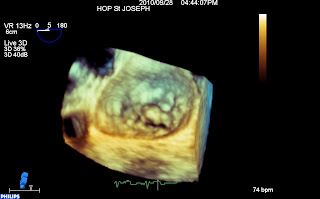

Vue 3D dite « chirurgicale », aorte en haut, auricule au gauche de l’écran, grande valve en haut avec un prolapsus médian et petite valve en bas :

Mitrale 3D from fish Nip echocardiographie on Vimeo.

Enfin, on note une dilatation et surtout une déformation importante de l’anneau (donc plutôt un type 1), qui est quasiment rond. Sur cette reconstruction tridimensionnelle de l’anneau en télésystole, les zones de restrictions paraissent en bleues, la zone prolabant (A2) est jaune. l’aorte est en haut, AL est la commissure antero-latérale.

Sur cette reconstruction 3D, on peut voir, dans le cadre en bas à droite, le petit carré bleu qui correspond au plan de l’anneau. Seul le A2 est au plan de l’anneau, le reste des feuillets sont en dessous, confirmant la restriction.